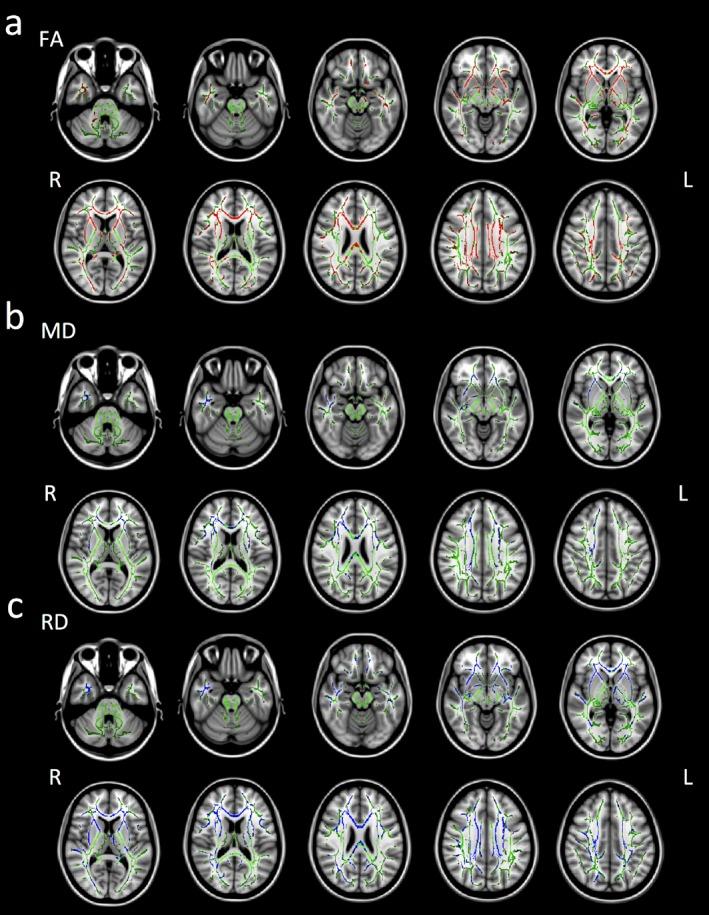

The subjects were 15 patients with TLE and 17 healthy controls. Mean duration of illness in the TLE group was 21.6 years. Tract-based spatial statistics (TBSS) were used for diffusion tensor imaging (DTI) analysis. Four diffusion tensor metrics, that is, fractional anisotropy (FA), mean diffusivity (MD), axial diffusivity (AD), and radial diffusivity (RD) were calculated and then examined for differences between the TLE and healthy control groups. We also examined for correlations between DTI parameters and duration of illness in the TLE group.

In the TLE group, compared with the healthy control group, FA was reduced, and MD and RD were increased, not only in the limbic and temporal lobe regions and their directly connecting regions in both hemispheres, but also in remote white matter regions. Duration of illness showed a significant negative correlation with mean whole-brain FA and a significant positive correlation with both mean whole-brain MD and RD. Brain regions showing correlation between disease duration and DTI metrics also extended to the limbic area and its connecting regions, and to remote white matter regions.